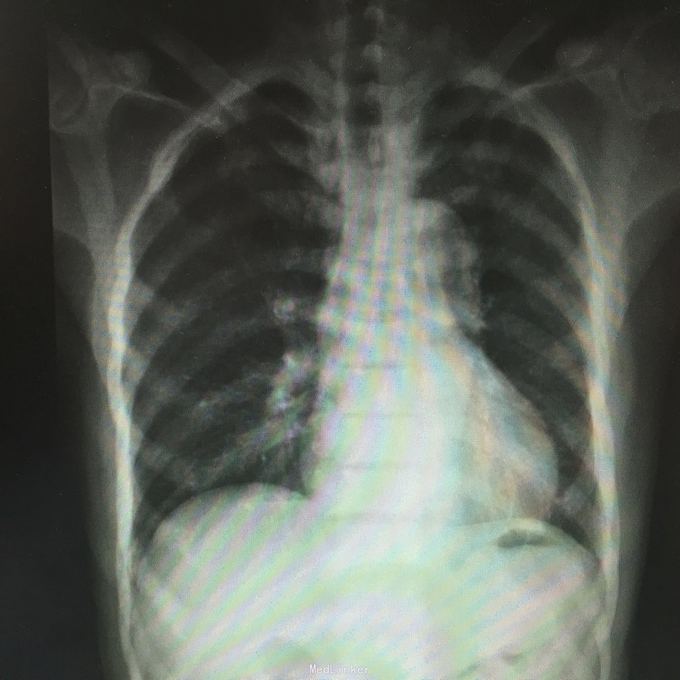

total PSA>100;前列腺磁共振平扫示:前列腺外周带左后方肿块,DWIBS信号明显增浓,考虑前列腺Ca。 行会阴前列腺穿刺活检术,病理示:前列腺腺癌。 全身骨扫描示:超级骨显像,符合前列腺Ca并多发骨转移。

前列腺癌并多发骨转移 处理:给予康士德,诺雷德,唑来磷酸等抗肿瘤治疗,提高免疫力等治疗,根据病情发展必要时给予放化疗及针对骨转移的锶89治疗